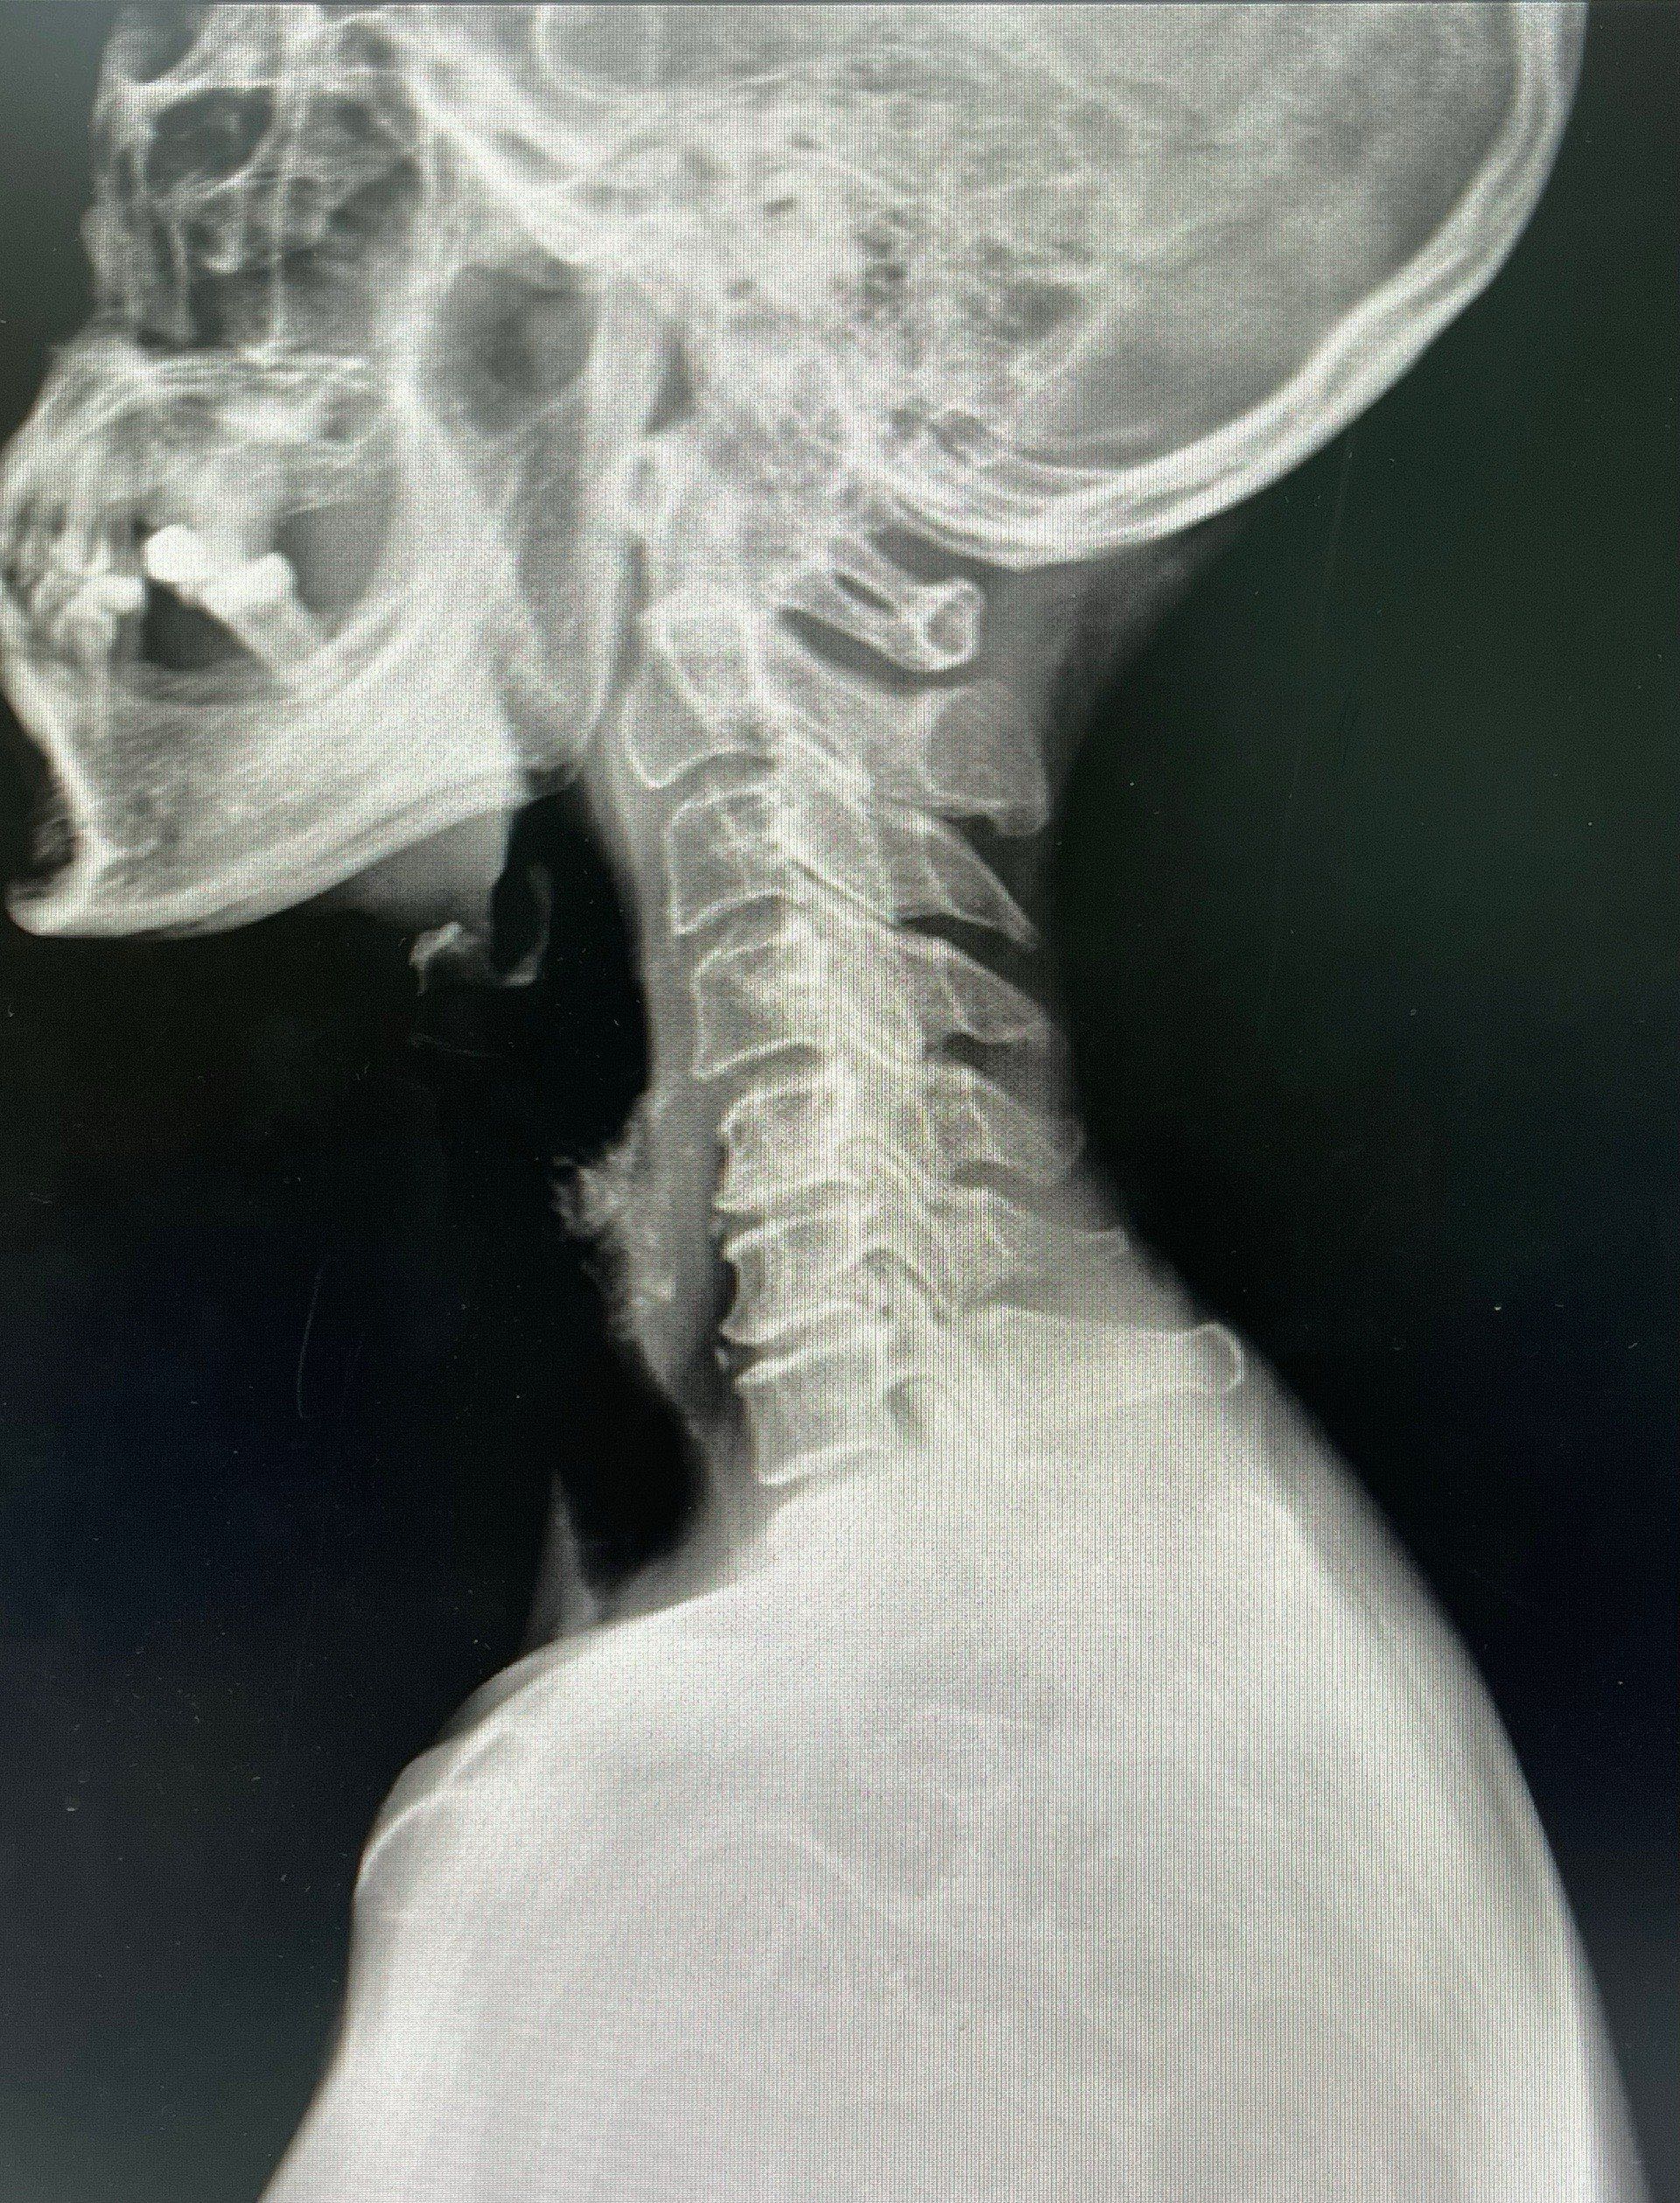

1. การตรวจสอบและประเมินอาการ: แพทย์จะทำการตรวจร่างกายและประเมินอาการของผู้ป่วยเพื่อกำหนดตำแหน่งที่ต้องฉีดยา โดยจะพิจารณาจากอาการปวดและผลการตรวจภาพเชิงลึก เช่น MRI หรือ CT Scan